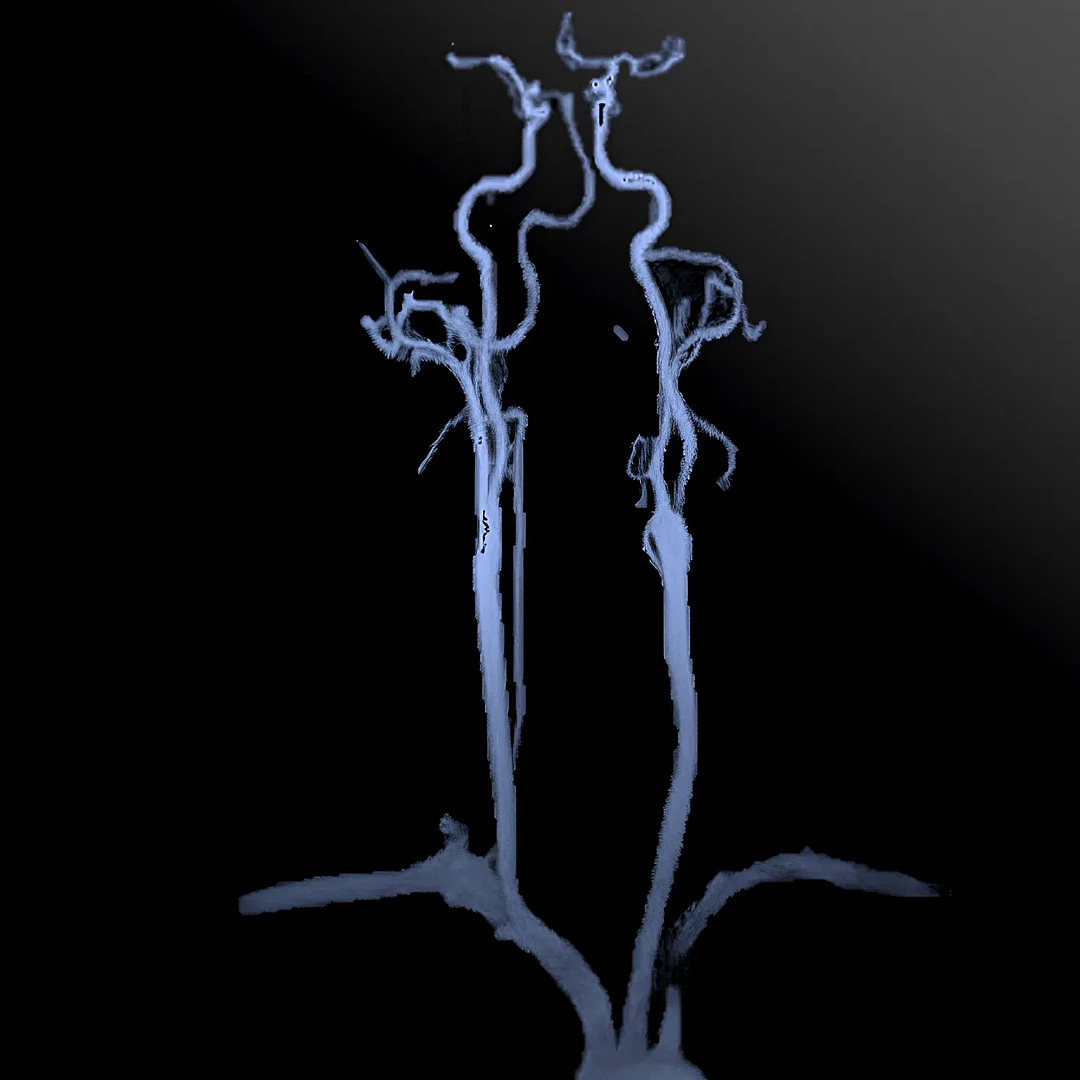

Brain and Neck MR Angiography is a non-invasive scan that visualizes blood vessels to detect blockages, aneurysms, or vascular malformations. It provides detailed insights into cerebral and neck circulation without the need for contrast dyes or radiation.